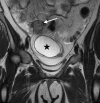

Case presentation: A 16-year-old female presented to the emergency department with acute onset of right lower quadrant abdominal pain for several hours. The patient was afebrile and physical examination was notable for isolated tenderness in the right lower quadrant. Ultrasound and computed tomography demonstrated an adnexal cystic structure. Pelvic magnetic resonance imaging was ordered to better characterize the pathology.

Discussion: Isolated fallopian tube torsion is an uncommon entity requiring prompt surgical intervention. Recognition and appropriate management are essential.